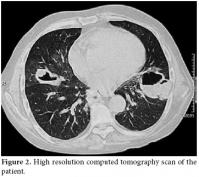

A 50-year-old male patient was admitted to our hospital with symptoms of fatigue, proximal muscle weakness, and bruising. Two years previously, he had manifested symptoms of arthralgia, arthritis, and edema. Because of these complaints, laboratory tests were performed. Nephrotic range proteinuria, a high creatinine level, bicytopenia along with antinuclear antibody (ANA) and Anti-deoxyribonucleic acid (anti-DNA) positivity were determined in these tests. Systemic lupus erythematosus was considered. Type ΙV lupus nephritis was also determined with a kidney biopsy. Endoxan 500 mg pulse and methylprednisolone 1000 mg pulse (3 days) were given to the patient parenterally. After these immunosuppressive treatments, the symptoms of the patient relieved, and corticosteroid treatment was continued as methylprednisolone 1 mg/kg/day at another hospital. The methylprednisolone dosage was not tapered accordingly, and after four months, suffering from fatigue, proximal myopathy, and weakness and the patient was admitted to our clinic. Upon physical examination, no other finding other than proximal muscle weakness was determined. Laboratory findings were white blood cell count: 12300/mm3, hemoglobin: 8.9 g/dl, hematocrit: 24%, MCV: 82 fL, lymphocyte: 200 mm3, platelet: 63000 mm3. Glucose: 79 g/dl, BUN: 109 mg/dl, creatinine: 2.7 mg/dl, uric acid: 8.4 mg/dl, Na: 135 mmol/L, K: 4.6 mmol/L, Cl: 105 mmol/L, Calcium: 8.2 mg/dl, P: 4.0 mg/dl, AST: 12U/L, ALT:39 U/L, LDH: 643 U/L, ALP: 70 U/L, and anti-dsDNA of 1:1280. Total bilirubin: 0.48 mg/dl, direct bilirubin: 0.06 mg/dl, Indirect bilirubin: 0.42 mg/dl, total protein: 5 g/dl, albumin: 2.39 g/dl, Fe: 73 mcg/dl, Iron binding capacity: 212 mcg/dl., PT: 11.1 sn, aPTT: 18.8 sn, INR: 0.90 were found. A chest radiograph taken on admission revealed multiple cavitary lesions (Figure 1). A chest computed tomography (CT) also showed multiple cavitary lesions at the sites of the right medial lobe, right inferior lobe superior segment, and left lingula inferior segment along with nodular lesions at the right inferior lobe superior segment (Figure 2). These lesions were found to be related with intensive and long-term steroid treatment. The cavitary lesions were considered as an opportunistic fungal infection, nocardiosis, or tuberculosis. A smear of sputum was negative for both Gram stain and acid fast bacilli, and cultures related to tuberculosis were found to be negative. A bronchoscopy and endobronchial lavage were performed to determine the etiology of these lesions. No endobronchial lesion was observed. Cultures for tuberculosis, nocardiosis, and fungal infections were taken from bronchoalveolar lavage, and also samples were taken for cytologic examination of lavage. In bronchoalveolar lavage fluid cytology, polymorphonuclear leukocytes was detected, and there were no atypical findings. The sputum specimen was also examined again, and cultures were sterile. The symptoms of the patient had increased progressively. The cavitary lesions had also increased. Because of this progression, high resolution computed tomography (HRCT) was performed. New cavitary lesions were determined at the left pulmonary site in HRCT. Nocardiosis was found positive in bronchoalveolar lavage fluid specimens. The patient was diagnosed as having pulmonary nocardiosis and given intravenous trimethoprim-sulfamethoxazole (320 mg/1600 mg/day), but the patient’s clinical findings worsened. Acute respiratory failure developed on the second day of treatment. Metabolic acidosis and respiratory alkalosis were added to the clinical findings. In arterial blood gas, PH: 7.31, PCO2: 24.8 mmHg, PO2: 35.6 mmHg, HCO3: 12.2 mmol, O2 saturation: 57.9% were found. Oxygen inhalation and anti-obstructive treatment were started. Sepsis and acute respiratory distress syndrome were considered possible , and the patient was sent to the intensive care unit. The patient died one day after being sent to the intensive care unit.

Pulmonary nocardiosis produces an impressive variety of roentgenographic findings, such as segmental infiltrates, lobar infiltrates, small and large cavities, necrotizing bronchopneumonia, necrotizing lobar pneumonia, lobar pneumonia with bulging fissures, small and large abscesses, single or multiple nodules, miliary patterns, masses with central cavitations, pleural effusion, and empyema.[5] Because the radiographic feature of nocardiosis is non-specific and pleomorphic with clinical findings ranging from malaise to respiratory failure, it is difficult to diagnose; therefore, the diagnosis of nocardiosis is often delayed. Multiple nodules and cavitation are more commonly described in acquired immune deficiency syndrome (AIDS) patients.[6,7] Multiple cavitary lesions are very rare in non-HIV patients. In our case, the patient was a man with a diagnosis of SLE, and he had undergone corticosteroid treatment for a long time. Although his test was negative for AIDS, multiple cavitary lesions were seen in his chest X-ray and HRCT. Since the patient was HIV-negative and immunosuppressive, all causes of multiple cavitary lung lesions were investigated. Tuberculosis, fungal infections, and malignancy were considered in the differential diagnosis. Multiple cavitary pulmonary nodules can be easily confused with a variety of other bacterial infections of the lung, including actinomycosis and tuberculosis as well as fungal infections and malignancies. In our patient, all of these causes were eliminated after all of the necessary tests were performed.